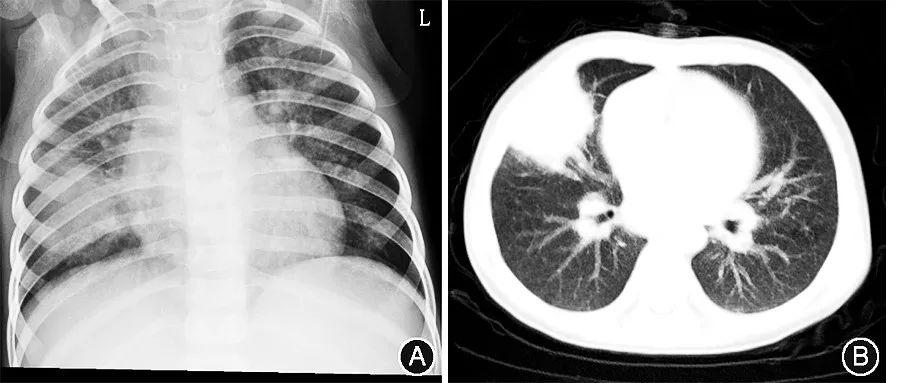

辅助检查:1年前当地三甲医院第一次结肠镜检查提示:降结肠、乙状结肠、直肠黏膜广泛充血、水肿,质脆,易出血,溃疡广泛分布,可见分泌物,边缘出血。肠镜病理活检标本显示:(结肠)黏膜组织慢性炎症急性活动伴间质嗜酸性粒细胞浸润并炎症渗出,局部间质内查见少许多核巨细胞,呈肉芽肿性炎改变。结核菌素试验(++),抗酿酒酵母菌抗体(IgA、IgG)阳性。至外地三甲医院第二次结肠镜提示克罗恩病L3活动期,十二指肠多发溃疡。半年前外地三甲医院外周血曲霉菌免疫学试验0.111(正常值0~0.5)。γ干扰素释放结核感染T细胞斑点试验:结核感染T细胞(A抗原)0,结核感染T细胞(B抗原)0。胸部CT提示肺部感染,考虑真菌感染可能性大。本次住院检查:血IgG 11.19 g/L,IgA 1.3 g/L,IgM 1.33 g/L,补体C3 1.7 g/L,补体C4 0.24 g/L。淋巴细胞免疫分析:总T淋巴细胞比例0.488、NK细胞比例0.335、辅助/诱导T淋巴细胞比例0.270、抑制/细胞毒T淋巴细胞比例0.210、B淋巴细胞比例0.205。真菌葡聚糖试验:236.38 pg/ml (正常0~69.99 pg/ml)。此次住院血常规规示白细胞9.39×10^9/L,中性粒细胞4.12×10^9/L,淋巴细胞4.45×10^9/L,红细胞3.88×10^12/L,红细胞平均体积74.5 fl(正常82~96 fl),平均红细胞血红蛋白含量24 pg(正常27~32 pg),平均红细胞血红蛋白浓度322 g/L(正常320~360 g/L),血红蛋白93 g/L,血小板473×10^9/L,超敏C反应蛋白4.5 mg/L。由于外院已行CT检查,为避免重复辐射,我院开始抗真菌治疗前只摄胸X线片,提示右肺中下野可见大片模糊片絮影,考虑肺炎(图1A)。抗真菌治疗3个月后摄胸部CT片,提示:右肺中叶仍可见大片高密度影,并可见条索影与肺门相连(图1B)。提示抗真菌疗效不佳。